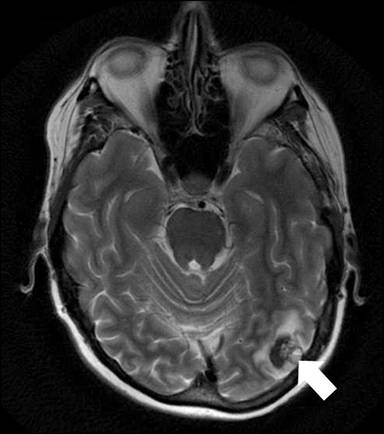

A 61-year-old female with history of hypertension, hyperthyroidism and depression presented with a one-day history of bilateral painless bluish discoloration of multiple toes. She was not on anticoagulants or any drugs known to induce vasospasm. She denied cocaine, tobacco or alcohol use. Family history was significant for colon cancer in her father. At admission, she was afebrile, with a blood pressure of 118/76 mmHg, a regular heart rate of 112 beats per minute and a respiratory rate of 22 per minute. Abdominal examination revealed hepatomegaly. She had bilateral bluish-black discoloration of multiple toes suggestive of a dry gangrene (Figure 1). The rest of her physical examination was unremarkable. New T-wave inversions in the inferolateral leads were revealed at electrocardiography. Initial blood tests demonstrated moderately elevated cardiac and liver enzymes (Table 1). Doppler study of lower extremities revealed bilateral thromboses of peroneal veins without any evidence of arterial occlusive disease. A transthoracic echocardiogram was normal. CT angiogram of chest and abdomen showed acute bilateral subsegmental pulmonary emboli and multiple hypodense hepatic lesions, along with a 3 cm mass arising in the pancreatic tail (Figure 2). This prompted therapeutic anticoagulation with unfractionated heparin. Over the course of the next 48 hours, she developed dysarthria, limb weakness and altered sensorium. A magnetic resonance angiogram of the head showed diffuse embolic infarctions with a large area of hemorrhagic transformation in the left temporal lobe (Figure 3). Extensive laboratory testing for an underlying hypercoagulable state was negative and serum CA 19-9 level was markedly elevated (Table 1). Fine needle aspiration biopsy from the liver lesions was consistent with metastatic adenocarcinoma (Figure 4). The diagnosis of metastatic pancreatic cancer was made based on the presence of a pancreatic mass, positive tumor markers and histopathology findings. Subsequently, the patient’s family opted for a transfer of care to a specialized oncology center, where she eventually expired several weeks later.

Figure 3. T-2 weighted magnetic resonance imaging demonstrating a 1.5 cm area of intraparenchymal hemorrhage in the posterior left temporal lobe (white arrow). |